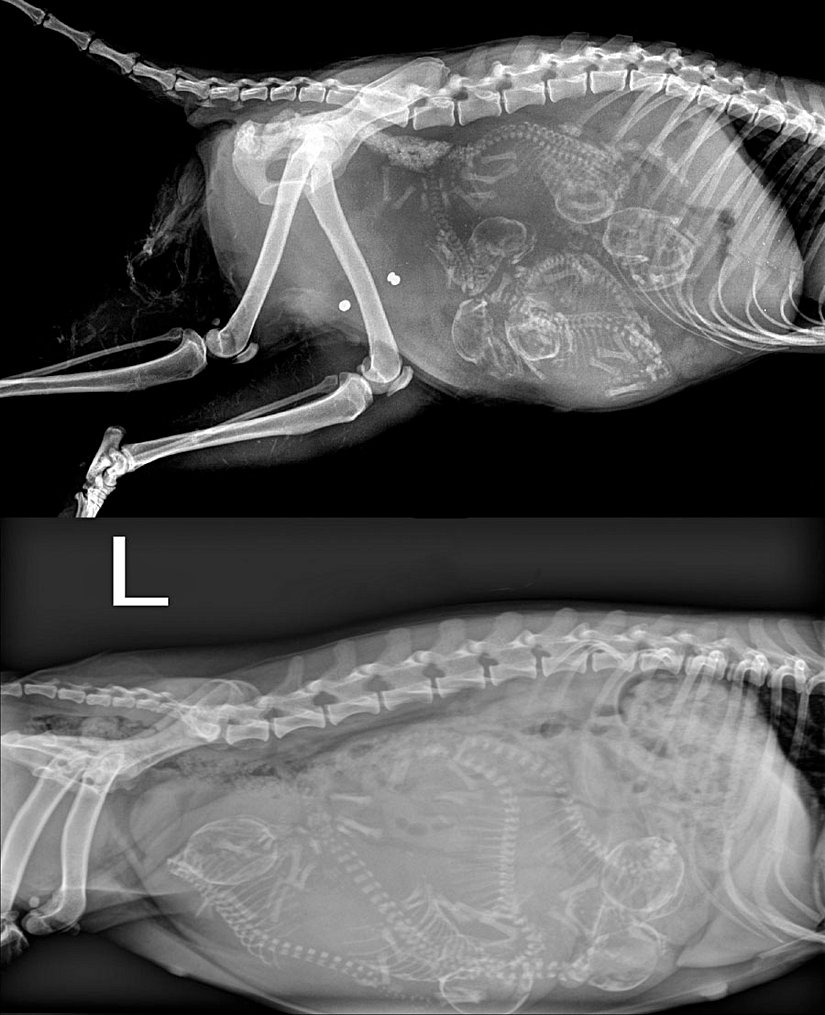

Aşağıda, muhteşem iki kare! Bu fotoğrafta üstte gördüğünüz görüntü, bir köpeğin hamileliği sırasında çekilmiş bir X-Işını taramasıdır. Alttaki ise, aynı durumdaki bir kediye aittir.

Bir kedi her gebelikte 1-8 yavruyu karnında taşıyabilir, yılda 2-3 kez hamile kalıp doğum yapabilir. Ömrü boyuncaysa bir dişi kedinin 100'ü aşkın yavrusu olabilir! Sadece bir çift kediden başlayarak, sadece 7 sene içerisinde ortalama 420.000 kedi doğması sağlanabilir! Köpeklerde de durum benzerdir.

Ortalamada bir köpek, hamileliği sırasında 1-10 arası yavruyu karnında taşıyabilir. Fakat köpekler genellikle biraz daha yavaş ürerler. Bu nedenle, sadece bir çift köpekle başladığınızda 6 sene içerisinde ortalamada 67.000 köpeğe ulaşabilirsiniz.